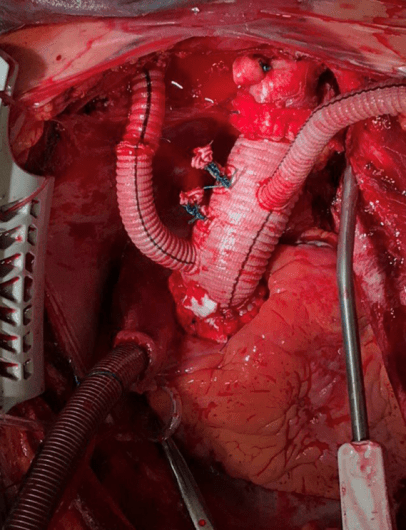

Оперативное вмешательство: в декабре 2021 по срочным показаниям выполнена операция-резекция восходящего отдела и дуги аорты, протезирование восходящей аорты и дуги по методике «полудуга» с реимплантацией брахиоцефального ствола в условиях искусственного кровообращения и кровяной холодовой кардиоплегии и антеградной церебральной перфузии.